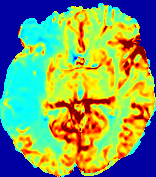

LesionRefer to captionRefer to captionRefer to captionRefer to captionRefer to captionRefer to caption𝐕rgbsubscript𝐕𝑟𝑔𝑏{\bf{V}}_{rgb}Refer to captionRefer to captionRefer to captionRefer to captionRefer to captionRefer to caption𝐕2subscriptnorm𝐕2{\|\bf{V}}\|_{2}Refer to captionRefer to captionRefer to captionRefer to captionRefer to captionRefer to captionRefer to caption3.53.53.52.82.82.82.12.12.11.41.41.40.70.70.70.00.00.0(mm/s)𝑚𝑚𝑠(mm/s)D𝐷DRefer to captionRefer to captionRefer to captionRefer to captionRefer to captionRefer to captionRefer to caption0.0200.0200.0200.0160.0160.0160.0120.0120.0120.0080.0080.0080.0040.0040.0040.0000.0000.000(mm2/s)𝑚superscript𝑚2𝑠(mm^{2}/s)Slice #1Slice #2Slice #3Slice #4Slice #5Slice #6

Figure 4: PIANO feature maps for another patient in the ISLES 2017 training set, where the lesion is located in the right hemisphere. Top row: segmented stroke lesion region (white) on different slices. The corresponding slices for the PIANO feature maps are shown in the following rows.

For a better insight into an estimated velocity field 𝐕𝐕{\bf{V}} and diffusion field 𝐃𝐃{\bf{D}}, we compute the following maps: (1) 𝐕rgbsubscript𝐕𝑟𝑔𝑏{\bf{V}}_{rgb}: Color-coded orientation map of 𝐕=(Vx,Vy,Vz)T𝐕superscriptsuperscript𝑉𝑥superscript𝑉𝑦superscript𝑉𝑧𝑇{\bf{V}}=(V^{x},V^{y},V^{z})^{T}, obtained by normalizing 𝐕𝐕{\bf{V}} to unit length and mapping its 3 components to red, green, blue respectively; (2) 𝐕2subscriptnorm𝐕2\|{\bf{V}}\|_{2}: 222 norm of 𝐕𝐕{\bf{V}}; (3) D𝐷D: scalar field in Eq. 5.

Fig. 3 and Fig. 4 show the PIANO feature maps estimated from two ISLES 2017 patients: all are highly consistent with the lesion in both cases. Details of the blood flow trajectories are revealed in 𝐕rgbsubscript𝐕𝑟𝑔𝑏{\bf{V}}_{rgb} by the ridged patterns and the sharp changes of colors in the unaffected (right) hemisphere, while the flat patterns appearing within the lesion provide little directional information about the velocity and indicate low velocity magnitudes. Velocity magnitudes are more directly visualized via 𝐕2subscriptnorm𝐕2\|{\bf{V}}\|_{2}, from which one can easily locate the lesion where 𝐕2subscriptnorm𝐕2\|{\bf{V}}\|_{2} is low. D𝐷D also indicates lower diffusion values in the lesion, though with less contrast potentially due to the fact that it captures the accumulated effect of CA diffusion at the voxel-level.